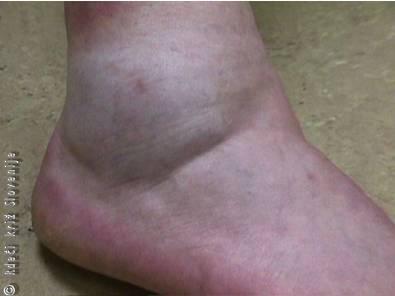

Slika 2

Zvin prepoznamo po oteklini podplutbi ter boleči in zavrti gibljivosti. Pri oceni pomaga primerjava z nepoškodovanim udom.

25-letni moški je pri igranju košarke doskočil na soigralčevo stopalo. Pri tem se je stopalo zvrnilo navznoter. Močno ga je zabolelo in na nogo zaradi bolečine ni mogel stopiti. Bolečina je čez nekaj minut nekoliko popustila in šepajoče je prišel v urgentno ambulanto. Ob pregledu (Slika 2) je bil poškodovani gleženj v primerjavi z zdravim močno otekel, podplut. Gibljivost je bila omejena in predel je bil boleč. Boleč je bil pritisk na zunanjo sklepno špranjo. Z rentgenskim slikanjem smo izključili zlom. Oteklina in bolečina bi bili ob pravilni prvi pomoči veliko manjši.